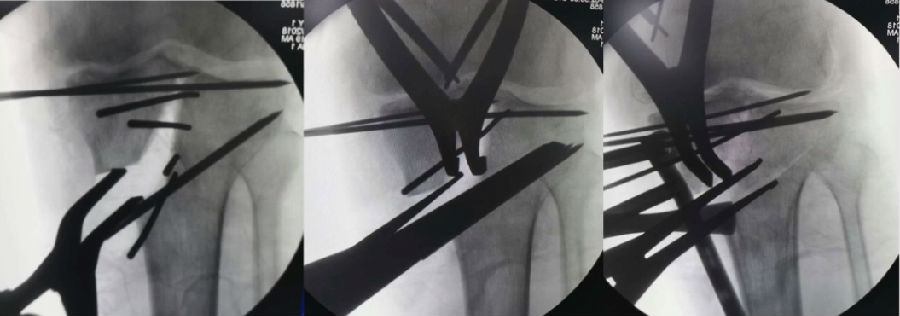

术中先打克氏针确定截骨方向,先做关节内截骨,截完后测量下肢力线,发现并没达到术前设计的Fujisawa点。

术中影像资料

随后用骨刀继续向前敲,做HTO内侧开放楔,截骨完成后内侧固定,并测量下肢力线,此时达到术前设计的要求。

该患者撑开较大,取了髂骨进行植骨。

髂骨植骨